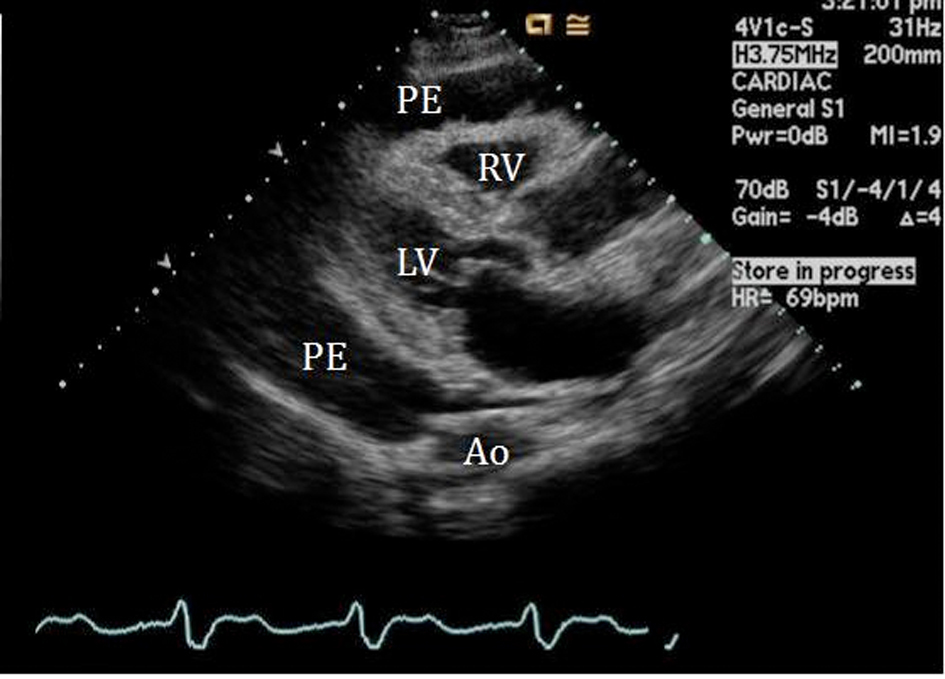

An initial complete blood count showed a mild anemia with hemoglobin of 11.2 g/dl. An anterior-posterior chest x-ray showed bilateral interstitial edema with pleural effusions. A transthoracic echocardiogram was performed and found a large pericardial effusion (Fig. 1) with tamponade physiology (Fig. 2). No intracardiac masses were noted. A right heart catheterization was also performed. The initial right atrial (RA) and intrapericardial pressures were elevated at 38 and 31 mmHg, respectively (Fig. 3). The patient underwent urgent pericardiocentesis after warfarin reversal with vitamin K and fresh frozen plasma. Approximately 1060 ml of blood-tinged fluid were removed. After pericardiocentesis there was no residual pericardial fluid assessed by transthoracic echocardiogram (Fig. 4), despite that the RA pressure remained significantly elevated at 33 mmHg. The RA tracing revealed a prominent Y descent (Fig. 5). Due to the patient’s supratherapeutic INR (international normalized ratio) and transient neurologic deterioration from sedation, simultaneous right and left heart catheterizations were not performed. The hemodynamics were compatible with effusive-constrictive pericarditis. Cytology and flow cytometry in the pericardial fluid revealed the presence of monoclonal kappa B-cells, CD 5 negative, CD 10, CD 19, CD 20, and CD 45 positive. Morphologically, the cells were consistent with large B-cell non-Hodgkin's lymphoma. A bone marrow biopsy ruled out systemic lymphomatous involvement. Positron emission tomography (PET) scan confirmed the diagnosis of primary cardiac lymphoma (PCL) showing thickening of the anterior pericardium with an standardized uptake value (SUV) of 5.0. There was no malignant uptake in any other structure such as lymph nodes, other serosal surfaces, or solid organs.

![]() Click for large image | Figure 1. 2-D Parasternal long axis view showing large pericardial effusion (PE) surrounding the right (RV) and left ventricle (LV). |